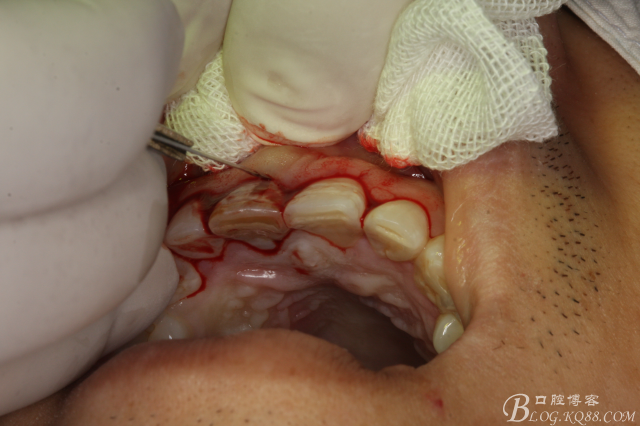

圖6.翻瓣、11唇側(cè)骨壁完全破壞、出乎意料。和根尖片影像資料出入過大。

圖8. 觸目驚心發(fā)現(xiàn)11唇側(cè)骨壁完全缺失,根充超填。預(yù)后難以判斷。